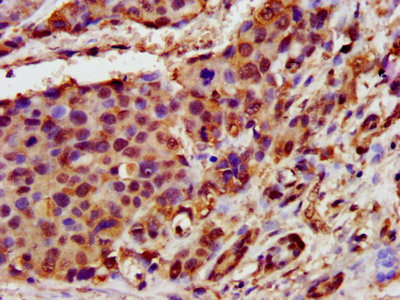

IHC image of CSB-PA872487LA01HU diluted at 1:400 and staining in paraffin-embedded human pancreatic cancer performed on a Leica BondTM system. After dewaxing and hydration, antigen retrieval was mediated by high pressure in a citrate buffer (pH 6.0). Section was blocked with 10% normal goat serum 30min at RT. Then primary antibody (1% BSA) was incubated at 4°C overnight. The primary is detected by a biotinylated secondary antibody and visualized using an HRP conjugated SP system.